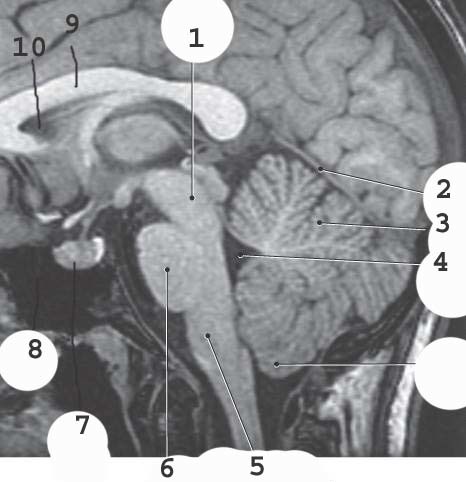

1

Midbrain

Longitudinal Fissure

2

corpus collosum genu

3

septum pellucidum

4

3rd ventricle

5

corpus collosum splenium

6

corpus collosum rostrum

Thalamus

Pineal gland

cerbral aqueduct